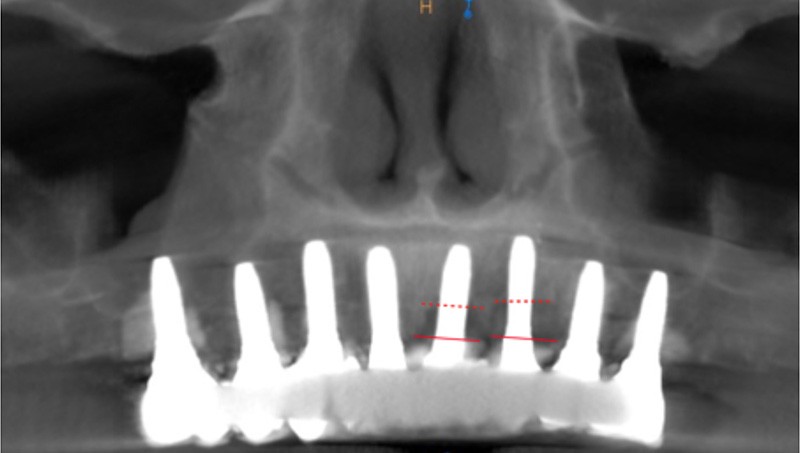

2 – Une méta analyse de 2016 [3] a évalué l’efficacité du traitement non chirurgical de la péri-implantite. Il s’avère que le traitement non chirurgical ne permet qu’une diminution de l’inflammation au niveau des tissus mous à court terme. En effet, on observe une diminution significative du saignement au sondage, mais pas de diminution efficace de la profondeur de sondage. En revanche, sans traitement chirurgical, on note une progression importante de la perte osseuse. Le traitement non chirurgical…